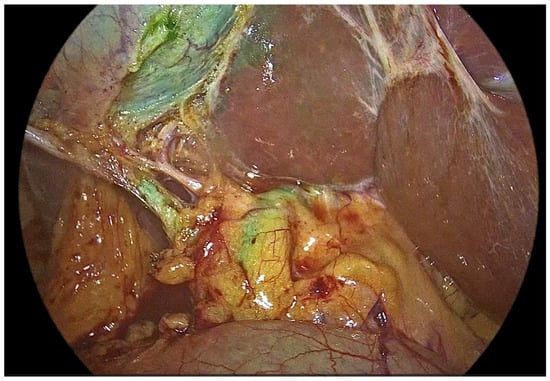

Comparative Evaluation of Standard Cholangiography, Intravenous, and Intracholecystic Indocyanine Green Fluorescence Cholangiography During Elective Laparoscopic Cholecystectomy: Results of a Three-Arm Randomized Trial

Background and Objectives: Bile duct injury is a relatively rare, but critical complication of laparoscopic cholecystectomy and is most commonly attributed to misinterpretation of biliary anatomy. Intraoperative biliary imaging may enhance anatomical recognition and reduce operative uncertainty, yet the optimal imaging modality remains debated. This study aimed to compare conventional intraoperative X-ray cholangiography with two fluorescence-based techniques—intravenous and intracholecystic indocyanine green fluorescence cholangiography—with respect to biliary visualization, perioperative outcomes, and surgeon satisfaction during elective laparoscopic cholecystectomy. Materials and Methods: This prospective, single-center, single-blind randomized controlled trial included 240 adult patients scheduled for elective laparoscopic cholecystectomy between June 2021 and December 2022. Participants were randomized equally to standard intraoperative cholangiography, intravenous indocyanine green fluorescence cholangiography, or intracholecystic indocyanine green fluorescence cholangiography. The primary outcome was successful visualization of predefined extrahepatic biliary landmarks, including the critical junction. Secondary outcomes included cholangiography duration, perioperative complications, postoperative inflammatory markers, and surgeon satisfaction assessed using a five-point Likert scale. This study was registered at ClinicalTrials.gov (NCT04908826). Results: Visualization rates of the critical junction and major extrahepatic bile ducts were comparable among three groups, with no statistically significant differences observed. Both fluorescence-based techniques achieved a 100% technical success rate, whereas standard cholangiography failed in a small proportion of cases. Cholangiography duration was significantly shorter in the fluorescence groups compared with standard cholangiography (p < 0.001). Surgeon satisfaction scores were significantly higher for both fluorescence approaches, with a slight preference for intravenous administration. Perioperative complication rates and postoperative inflammatory markers were com-parable among groups. Conclusions: Intravenous and intracholecystic indocyanine green fluorescence cholangiography are non-inferior to conventional intraoperative cholangiography for biliary anatomy visualization and offer advantages in procedural efficiency and surgeon satisfaction. Fluorescence-based imaging represents a safe and effective alternative for intraoperative biliary mapping during elective laparoscopic cholecystectomy. Full article

Show Figures

Figure 1